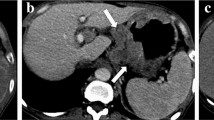

CT morphological characteristics

Readers one and two (with 5 and 7 years of experience in the diagnosis of abdominal imaging, respectively) who were blinded to clinicopathological information except for the general tumor location, assessed the morphological characteristics of each lesion on transverse CT images independently, and their results were used to evaluate interobserver reliability. The third reader (with twenty years of experience in abdominal imaging) confirmed their inconsistent opinions as the final result. CT morphological characteristics were as follows: (1) infiltrative growth (absent, present): defined as unclear border between the lesion and the normal gastric wall; (2) ulceration (absent, present); (3) adjacent adipose tissue stains (absent, present); (4) mucosal line status (interruption, thickening); (5) morphological type (thickening type, mass type); (6) linitis plastica (absent, present); and (7) lymphadenectasis (absent, present): defined as a short-axis diameter of the regional LN over 1 cm in the upper abdomen16.

CT morphological characteristics

Table 2 summarizes the results of CT morphological characteristics between HER2-negative and HER2-positive groups in the primary cohort. The morphological type differed significantly between the two groups in the primary cohort (p = 0.013, Table 2).

First, for CT morphological characteristics and conventional CT values, we found that thickening type lesions based on CT morphology were more common in HER2-negative GCs. It is also reported that most HER2-negative GCs tended to be diffuse types based on Lauren classification18,19,20. Tumor cells of diffuse type GCs are scattered in stomach wall and could not form obvious masses, which are more likely to display as thickening type on CT morphology. Accurate Lauren classification can only be accurately obtained by pathological evaluation of surgical specimens, while CT morphological characteristics are easy to evaluate preoperatively. In this study, CT value-related parameters based on the phase of 180 s delay, including DP value mean, DP value min, and Δmean D–N, were significantly higher in HER2-negative group in the primary cohort. It indicated that the enhancement degree in HER2-negative GCs were higher than in HER2-positive GCs in DP. Previous studies showed that HER2-negative GCs tended to be poorly differentiated and more aggressive18,19. Moreover, Tsurumaru et al. also reported that the CT values of undifferentiated type GCs were significantly higher than those of differentiated or mixed type in the delayed phase21. We reviewed relevant studies and found that CT parameters based on the phase of 180 s delay were widely used in the evaluation of hepatocellular carcinoma22,23,24. Sano et al. mentioned that the CT values based on the phase of 180 s delay were significantly different between hepatocellular carcinoma and intrahepatic cholangiocarcinoma22.